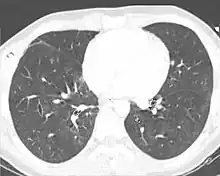

Chest X-ray is the most common method used for diagnosis,[37] and may be used to confirm a diagnosis already made using clinical signs.[20] Consolidated areas appear white on an X-ray film.[42] Contusion is not typically restricted by the anatomical boundaries of the lobes or segments of the lung.[27][43][44] The X-ray appearance of pulmonary contusion is similar to that of aspiration,[32] and the presence of hemothorax or pneumothorax may obscure the contusion on a radiograph.[25] Signs of contusion that progress after 48 hours post-injury are likely to be actually due to aspiration, pneumonia, or ARDS.[10]

Although chest radiography is an important part of the diagnosis, it is often not sensitive enough to detect the condition early after the injury.[35] In a third of cases, pulmonary contusion is not visible on the first chest radiograph performed.[7] It takes an average of six hours for the characteristic white regions to show up on a chest X-ray, and the contusion may not become apparent for 48 hours.[7][27][43] When a pulmonary contusion is apparent in an X-ray, it suggests that the trauma to the chest was severe and that a CT scan might reveal other injuries that were missed with X-ray.[2]

Computed tomography

Computed tomography (CT scanning) is a more sensitive test for pulmonary contusion,[6][33] and it can identify abdominal, chest, or other injuries that accompany the contusion.[38] In one study, chest X-ray detected pulmonary contusions in 16.3% of people with serious blunt trauma, while CT detected them in 31.2% of the same people.[45] Unlike X-ray, CT scanning can detect the contusion almost immediately after the injury.[43] However, in both X-ray and CT a contusion may become more visible over the first 24–48 hours after trauma as bleeding and edema into lung tissues progress.[46] CT scanning also helps determine the size of a contusion, which is useful in determining whether a patient needs mechanical ventilation; a larger volume of contused lung on CT scan is associated with an increased likelihood that ventilation will be needed.[43] CT scans also help differentiate between contusion and pulmonary hematoma, which may be difficult to tell apart otherwise.[47] However, pulmonary contusions that are visible on CT but not chest X-ray are usually not severe enough to affect outcome or treatment.[37]